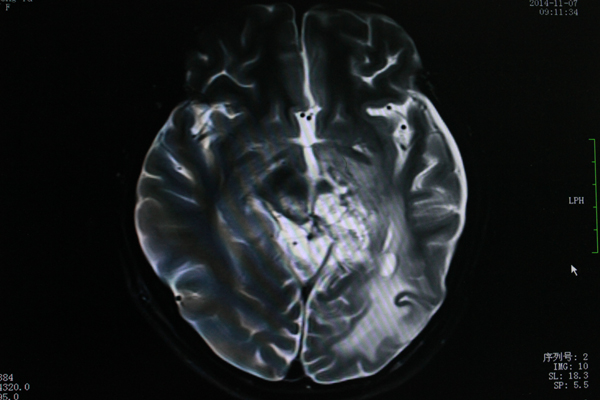

• 替莫唑胺辅以中药固本花季脑瘤少女重现欢颜

替莫唑胺辅以中药固本花季脑瘤少女重现欢颜

18岁的小雨本来应该在高三的课堂上,但是自2012年被查出患有左侧脑室管膜瘤,因头晕乏力休学在家,学校生活便离她远去了。所幸的是经过我院肿...